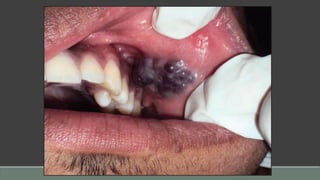

Kaposi’s Sarcoma

Etiology

• Several forms

◦ • Classic idiopathic form affecting extremeties

◦ • Endemic form (African)

◦ • Immunosuppression-associated form

◦ • Acquired immunodeficiency syndrome (AIDS)-associated form

• All forms, especially AIDS-associated and immunosuppressionassociated forms, may be

caused by or closely related to a herpesvirus (human herpesvirus 8 [HHV-8] or Kaposi’s

sarcoma–associated herpesvirus [KSHV]).

Clinical Presentation

• Classic form associated with slow but pernicious growth over many years; oral lesions rarely seen

• Endemic form more rapid; oral lesions rarely seen

• AIDS-associated KS most commonly seen on keratinized mucosa/mucoperiosteal tissues; strong

predilection for hard palate, followed by gingiva, buccal mucosa, and tongue (prevalence decreasing

with treatment for AIDS)

• Evolution from bluish macule to nodule(s)

• Evolution to multiple lesions

• May precede or follow cutaneous lesions

• Usually asymptomatic

Diagnosis

• Location and appearance

• May occur in up to one-third of AIDS patients

• Biopsy showing spindle cell proliferation with vascular slits, extravascular red blood cells

Differential Diagnosis

• Hematoma

• Hemangioma

• Ecchymosis

• Malignant melanoma

• Pyogenic granuloma

• Amalgam tattoo

Prognosis

• Variable, depending upon host’s immune status, but generally poor in AIDS-associated form